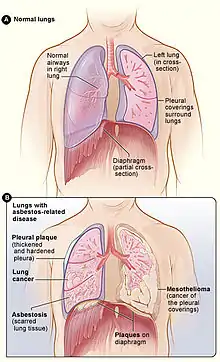

Asbestos

Asbestos are fibrous material that are found in many industrial buildings in Australia from the 1940s to 1987 . Exposure to asbestos occurs through inhalation of the particulates contained in these fibrous material, and they quickly become trapped and deposited in the airways and passages of the lungs.[11] As such, the exposure to asbestos increases the risk of developing cancers in the lung, ovary and pharynx.[12] The incidence of these cancers are said to occur decades after initial exposure to asbestos.[11] Products containing asbestos were eventually phased out towards the end of the 1980s, and a complete ban on asbestos was initiated in 2003. State and federal law in Australia have guidelines in their duty of care conduct of both employers and employees to reduce the risk of asbestos exposure.[12]